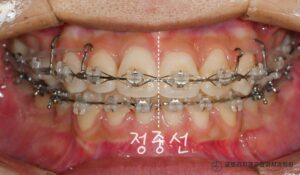

망우동 치과 정중선 편위 및 삐뚤어진 치열, 가지런한 배열을 회복하기 위한 발치 교정

안녕하세요 망우동 치과 김정은 원장입니다. 치아가 삐뚤어 교정 상담을 받게 되면 많은 분들이먼저 궁금해하시는 것이 바로 비발치 인지 발치 교정인지에 대한 부분입니다. 23.07.18 가능하다면 치아를 뽑지않고 배열만 정리하는 비발치 방식을…

Continue Reading망우동 치과 정중선 편위 및 삐뚤어진 치열, 가지런한 배열을 회복하기 위한 발치 교정